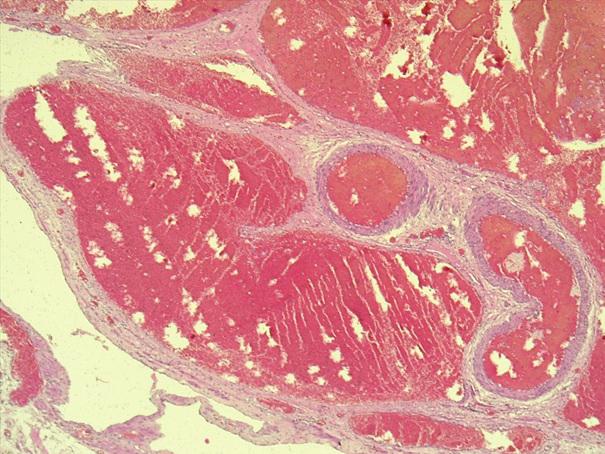

*Case 4 : Dr Dauda Suleiman

email: desuleiman@atbu.edu.ng

Clinical detail: Age: 65years

Presenting symptoms: PV bleeding; cervical mass

Please, consult the virtual slides of Case 4 below.